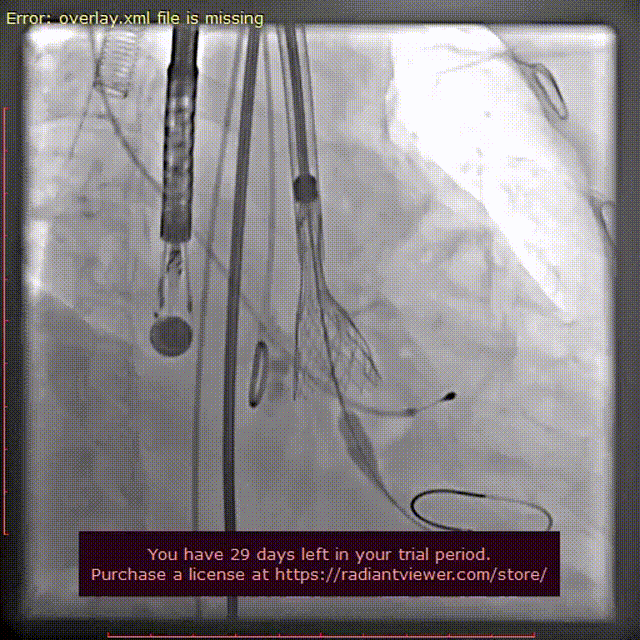

超声术后评估

超声显示最大流速降到2.3m/s,峰值压差21mmHg,假体瓣膜形态良好,工作正常,轻-中量瓣周漏。